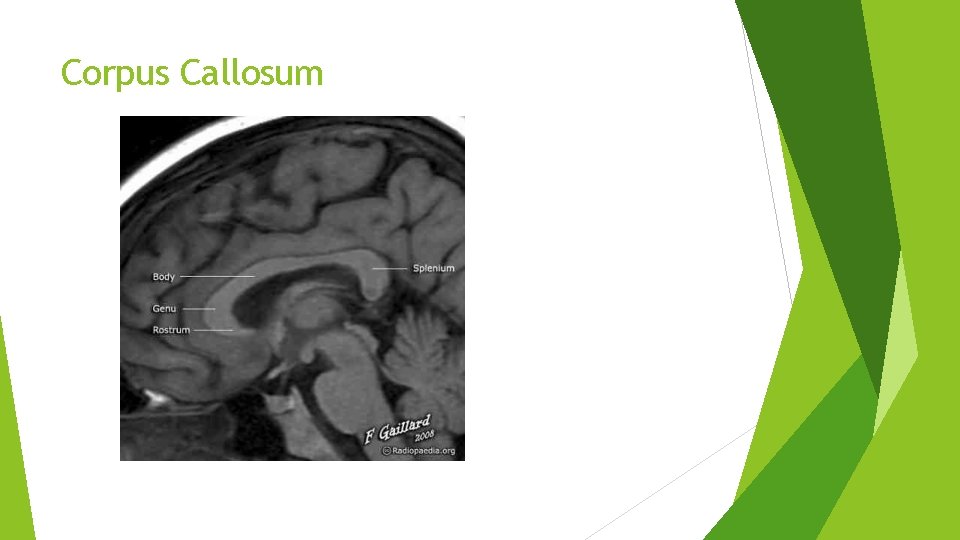

Corpus Callosum

INTRODUCTION � Definition: A rare CNS disease characterized by demyelination of the Corpus Callosum. � Discovered by two Italian pathologists Marchiafava and Bignami in 1903. � It affects the middle 2/3 rd of the Corpus Callosum � Common age of onset: 45 y/o men � Deficiency of Vitamin B complex has been implicated. � It has a high mortality rate (Of the 250 cases reported in 2001, 200 died (80%), 20 had a favorable outcome and 30 were severely disabled).